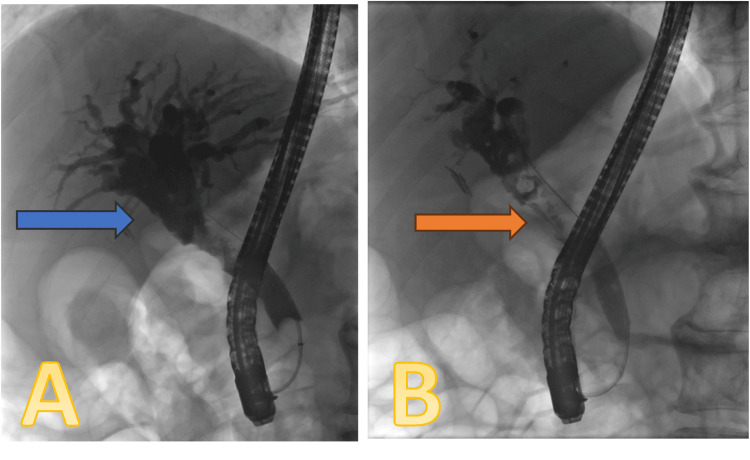

The patient underwent an endoscopic retrograde cholangiopancreatography (ERCP) procedure on November 18, 2023, which showed significant biliary dilation with the suggestion of a soft tissue lesion in the mid-CBD (Figure 2). Sphincterotomy was done, and the duct was trawled with a 12-15-mm balloon. Several small particles of debris and soft tissue were extracted, and brushing samples were taken from the lesion. A 7F x 7-cm double plastic stent was inserted, and a small piece of soft tissue was sent for histology.

A repeat ERCP was performed on January 24, 2024. The old stent was removed, and a cholangioscope was advanced into the bile ducts up to the hilum of the liver. There was an extensive polypoidal papillary lesion starting at 2 cm from the ampulla and extending proximally over 5 cm, stopping just 1 cm distal to the hilum. The tumour was circumferential in the mid-CBD, but the hilum appeared to be normal and uninvolved. Cholangioscopy-guided biopsies were taken along the lesion, and a 7 x 7 cm plastic double-pigtailed stent was inserted in the bile duct (Figure 3).